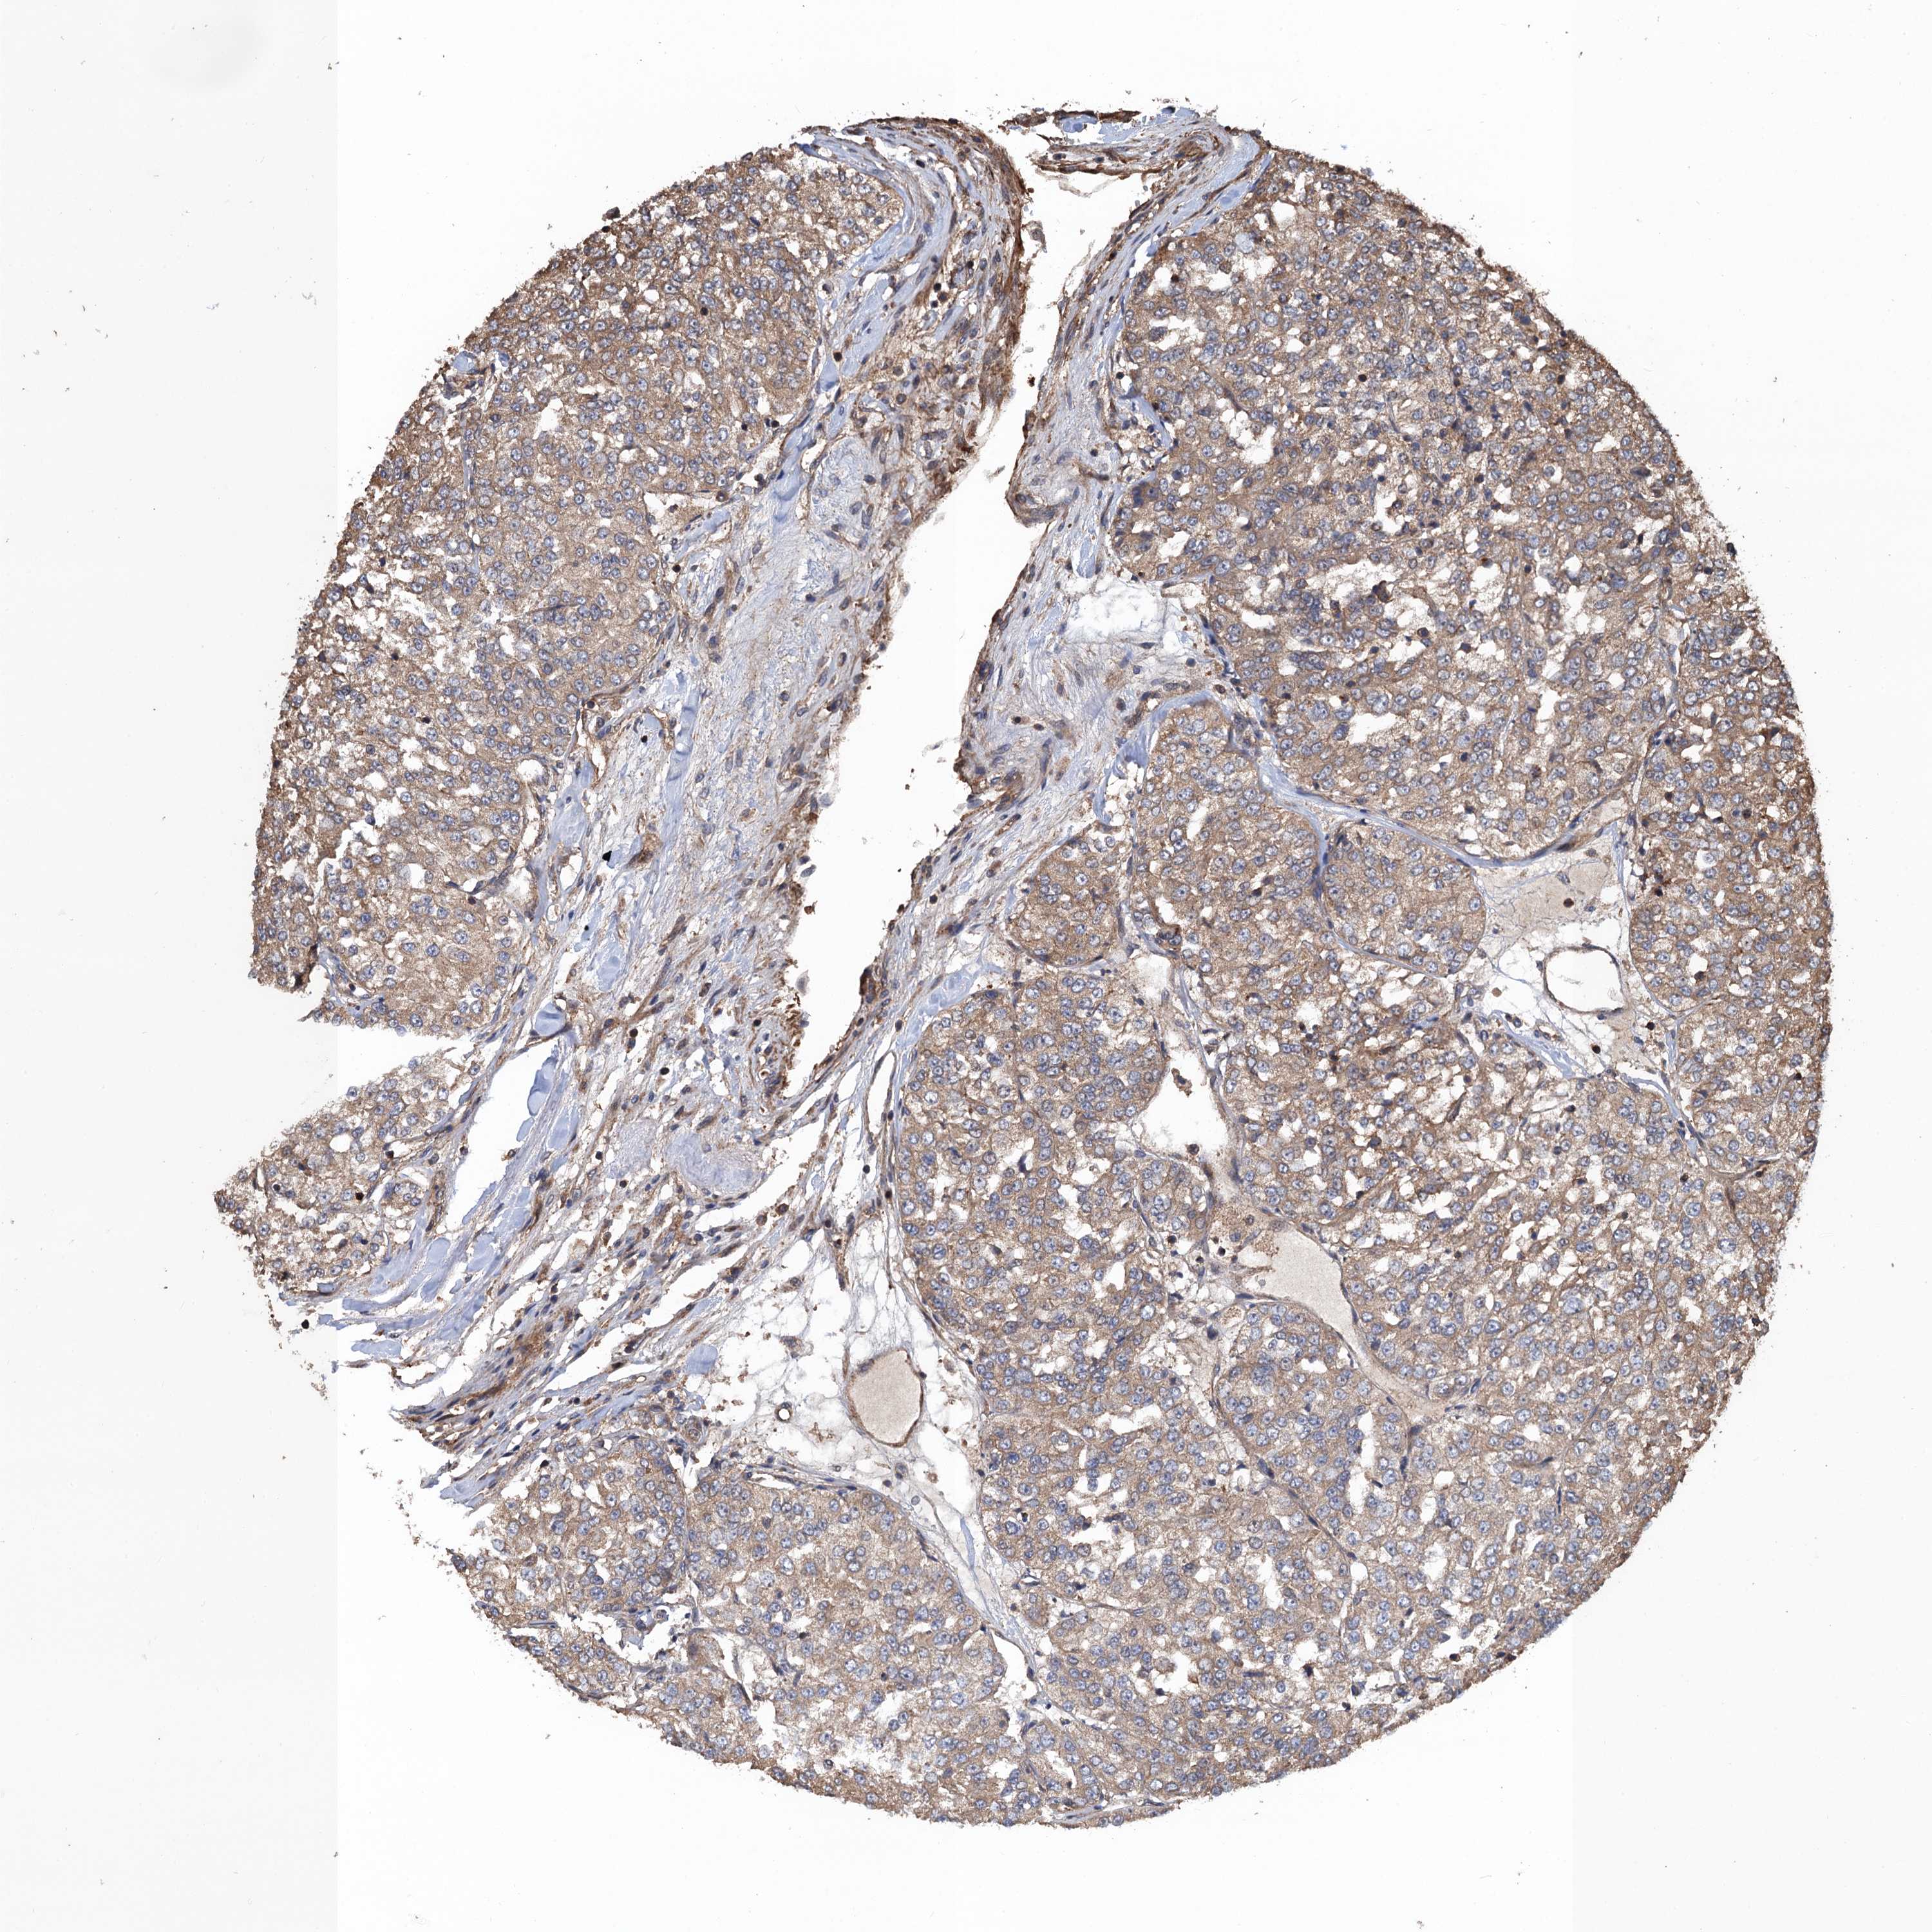

KIDNEY RENAL CLEAR CELL CARCINOMA (TCGA) - Interactive survival scatter ploti

The Survival Scatter plot shows the clinical status (i.e. dead or alive) for all individuals in the patient cohort, based on the same data that underlies the corresponding Kaplan-Meier plots. Patients that are alive at last time for follow-up are shown in blue and patients who have died during the study are shown in red.

The x-axis shows the expression levels (FPKM) of the investigated gene in the tumor tissue at the time of diagnosis. The y-axis shows the follow-up time after diagnosis (years). Both axes are complimented with kernel density curves demonstrating the data density over the axes. The top density plot shows the expression levels (FPKM) distribution among dead (red) and alive patients (blue). The right density plot shows the data density of the survived years of dead patients with high and low expression levels respectively, stratified using the cutoff indicated by the vertical dashed line through the Survival Scatter plot. This cutoff is automatically defined based on the FPKM cutoff that minimizes the p-score. The cutoff can be changed by dragging the vertical line or by entering a cutoff value in the square labeled "Current cut-off".

Under the Survival Scatter plot the p-score landscape (black curve; left axis) is shown together with dead median separation (red curve; right axis). Dead median separation is the difference in median mRNA expression between patients who have died with high and low expression, respectively. It is calculated as follows: median FPKM expression of dead patients with high expression - median FPKM expression of dead patients with low expression. This is intended to aid the user in visually exploring custom cutoffs and the associated p-scores and dead median separation.

Individual patient data is displayed and can be filtered by clicking on one or more of the category buttons on the top of the page. Categories describing expression level and patient information include: high, low, alive, dead, female, male and tumor stages. The scale of the x-axis can be toggled between linear and log-scale by clicking on the "x log" button. Mouse-over function shows TCGA ID, patient information and mRNA expression (FPKM) for each patient.

& Survival analysisi

Kaplan-Meier plots summarize results from analysis of correlation between mRNA expression level and patient survival. Patients were divided based on level of expression into one of the two groups "low" (under cut off) or "high" (over cut off). X-axis shows time for survival (years) and y-axis shows the probability of survival, where 1.0 corresponds to 100 percent.

PPP4R1 is potential prognostic, high expression is favorable in Kidney Renal Clear Cell Carcinoma (TCGA)

Best expression cut offi

Based on the FPKM value of each gene, patients were classified into two groups and association between prognosis (survival) and gene expression (FPKM) was examined. The best expression cut-off refers the FPKM value that yields maximal difference with regard to survival between the two groups at the lowest log-rank P-value. Best expression cut-off was selected based on survival analysis .

When clicking on this number, the vertical dashed line indicating cut-off, the interactive survival plot, and the Kaplan-Meier curve will be adjusted to show results based on the best expression cut-off.

: 17.64

P scorei

Log-rank P value for Kaplan-Meier plot showing results from analysis of correlation between mRNA expression level and patient survival.

N/A

TCGA RNA samplesi

RNA-seq data is reported as average FPKM (number Fragments Per Kilobase of exon per Million reads), generated by the The Cancer Genome Atlas (TCGA) .

Normal distribution across the dataset is visualized with box plots, shown as median and 25th and 75th percentiles. Points are displayed as outliers if they are above or below 1.5 times the interquartile range. FPKM values of the individual samples are presented next to the box plot.

Average pTPM 21.8

Number of samples 521